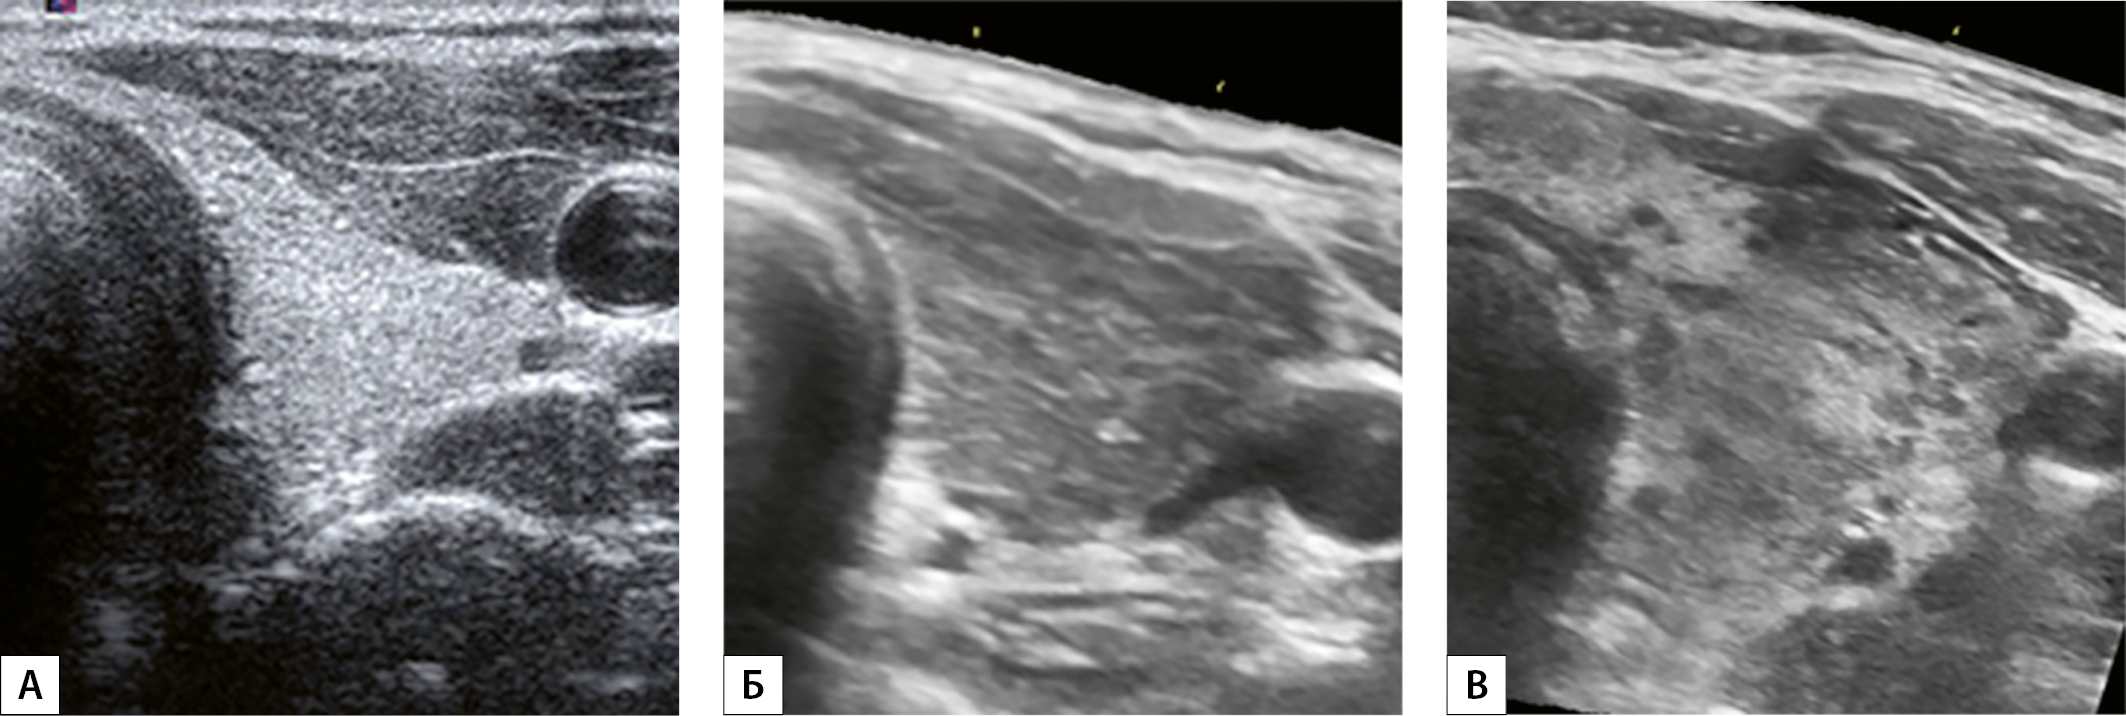

2. Рисунок 2. Эхограммы левой доли щитовидной железы, выполненные в поперечной плоскости сканирования на уровне среднего сегмента (перешейка) у больных тиреотоксикозом. А — эхогенность ЩЖ в норме, соответствует 40–60 единицам шкалы серого цвета. Б — эхогенность диффузно понижена, соответствует >60 единиц шкалы серого цвета. В — эхогенность локально понижена. Имеются участки >60 единиц шкалы серого цвета. Два признака «размеры» и «структура железы» не изменены.